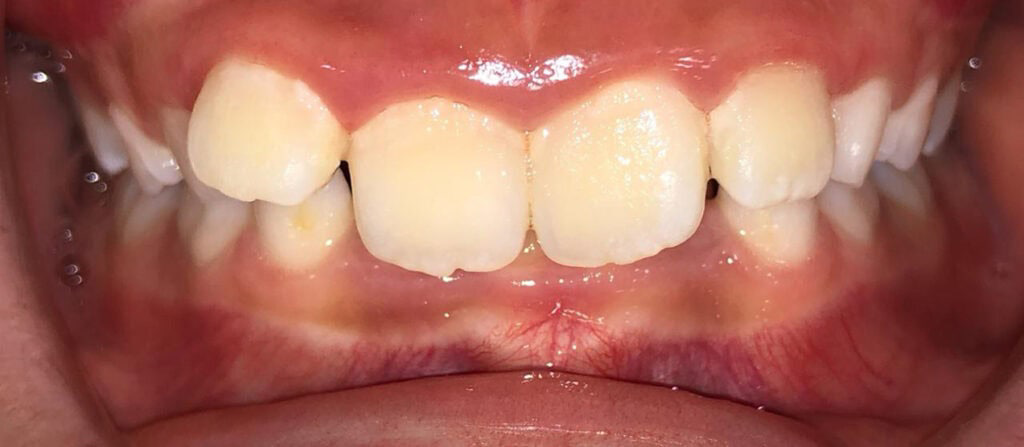

Actual Patient: Samuel

Samuel before1 img Samuel after1

Severe “Overbite”, BUCK TEETH, Narrow Jaws, Severe Deep Bite, Blocked out teeth

img Samuel before2 1 img Samuel after

Front View

Top View

Right & Left Sides